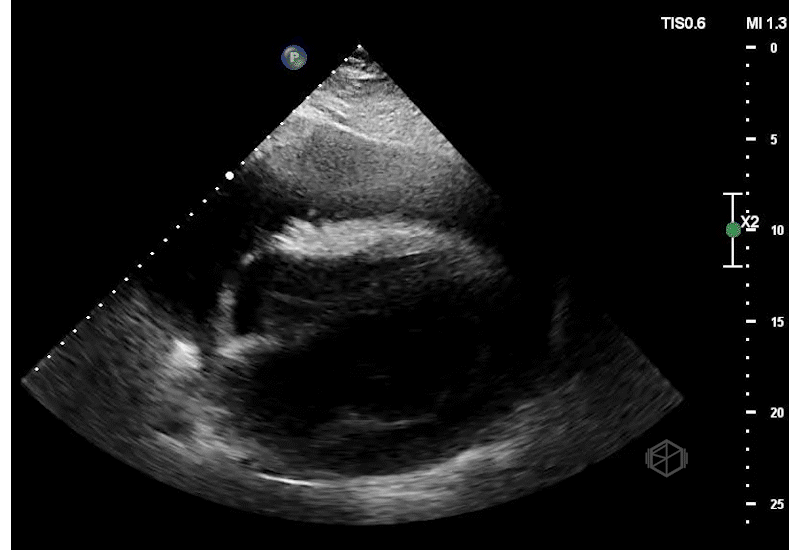

They did a POCUS echo and saw the following —

Not just rapid atrial fibrillation!

This is a massive pericardial effusion, measuring up to 5.0cm in it’s largest portion. There are signs of tamponade on this echo — aside from the obvious “swinging heart,” there is right ventricular diastolic collapse. The right ventricle does not get a chance to fully fill during diastole due to the extra-cardiac pressure from the pericardial effusion.

Diagnosis: Extra-large pericardial effusion with a side of tamponade

The patient had 1500ml of serosanguinous fluid drained by cardiology.